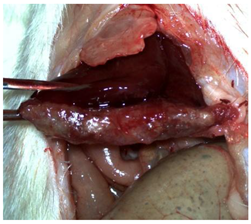

A well-established rat liver laceration model, known for its consistent induction of uncontrolled bleeding, was employed in this study [27]. Thirty-three male Wistar rats (weighing approximatively 350 g) were included. After intramuscular anesthesia (2:1 ketamine/xylazine), the surgical area was prepared. A xipho-subumbilical midline laparotomy allowed access to the left liver lobe, from where a 3 × 1.5 cm section was resected. Hemostasis was then achieved using one of three approaches: in the control group (C)—n = 5, bipolar electrocautery; in the study group (S)—n = 14, the novel CA–PLA hemostatic patch; and in the TachoSil® group (T)—n = 14, a fibrinogen/thrombin patch (TachoSil®—Corza Medical Gmbh., Jestetten, Germany), as presented in Table 1. Our study’s primary objective was to analyze the intracorporeal behavior of the new cyanoacrylate and polylactic acid hemostatic patch and compare it with Tachosil. For this reason, we allocated more subjects to these two key groups. We intentionally kept the control group smaller to adhere to the 3 Rs of ethical research: Reduce, Reuse, and Replace. For intraoperative footage concerning hemostasis, please refer to the Supplementary Materials (Videos S1–S3). Subsequently, the abdominal wall was closed with 4–0 polydioxanone sutures. Postoperatively, the rats were monitored for 24 h before being returned to their standard housing with ad libitum access to water and food.

The rats were observed for 150 days, with planned sacrifices at different time points (50, 100, and 150 days) to assess the liver resection site. After 50 days, five subjects from each of the S and T groups were sacrificed, followed by two more from each of these groups at 100 days. The remaining animals were sacrificed at the 150-day endpoint. For each sacrificed animal, the previously described anesthesia and laparotomy procedures were repeated. The clinical appearance of the abdominal cavity was documented, and after any adhesions were carefully dissected, tissue samples were harvested from the healed hepatic resection plane (approximately 3 × 0.5 cm strips) for histopathological analysis. Following the harvest procedure, the subjects were euthanized via an overdose of anesthetic.

The CA + PLA patch proved effective in achieving rapid hemostasis. Upon contact with the bleeding liver, it quickly polymerized and adhered, forming a hardened, shell-like barrier that immediately stopped blood flow. Observations at PO day 50 showed that the patch remained intact on the resection plane, alongside mild to moderate abdominal adhesions. By PO day 100, while the omentum largely covered the resection site, approximately 40% of the patch had degraded. By PO day 150, peritoneal adhesions were more significant (including stomach and small bowel involvement in two instances), yet the patch itself had undergone substantial degradation, with over 80% of its original size resorbed.

For the C group, the liver resection site showed minimal scarring and adhesions, consisting mainly of omental strips attached to the resected surface.

The subjects in the T group macroscopically displayed the fibrinogen/thrombin patch present at the resection plane at all time intervals. The patch appeared to thin over time, indicating its bioresorbable nature. Notably, this group developed the fewest peritoneal adhesions.

Table 2 illustrates the appearance of the hepatic resection plane for each study group at hemostasis and on postoperative days 50, 100, and 150.